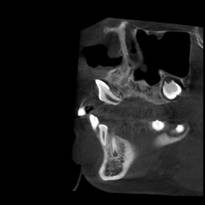

常规开展:数字化根尖片/横断牙合片、数字化口腔曲面体层片、头影测量侧位/正位片、手腕骨片、颅颌面CBCT、牙齿CBCT的检查以及涎腺造影、窦道 瘘管造影。

颅颌面CBCT

诊断范围涉及牙体牙髓病、牙周病、阻生牙/多生牙定位、种植牙术前CT评估分析、颞下颌关节CT诊断分析、,颌骨及涎腺疾病、颌面发育畸形、正畸治疗辅助诊断等大部分颌面部疾病,为临床医疗提供强有力的支持。